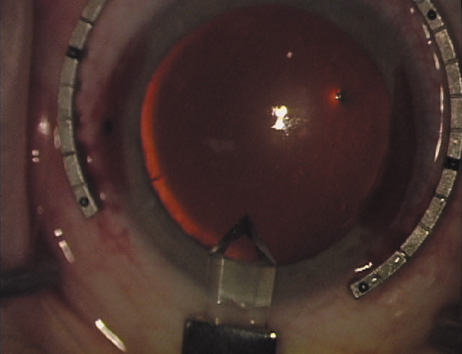

Case 2 is a 79-year-old woman who presented with a very dense left cataract. Her refraction was recorded at −2.25 +2.75 × 125 with a difficult end point. Her manual keratometry and topography measurements were consistent and revealed slightly less than 1.75 D at 120 degrees. Because of the questionable refraction, greater value was placed on the corneal measurements. Based upon the cataract nomogram, the plan was for paired LRIs of 40 degrees to be placed over the steep 120-degree axis (Figs. 1219).

Fig. 12. In this left eye, the steep meridian is at the 120-degree axis and has been delineated by opposing limbal marks. The upper left hand ink mark represents the 6:00 position for orientation. (Reprinted from Hardten DR, Lindstrom RL, Davis EA. Phakic Intraocular Lenses: Principles and Practice. Thorofare, NJ: SLACK Incorporated, 2004, with permission.)

Fig. 13. The incision is begun 20-degrees to one side of the centering mark. (Reprinted from Hardten DR, Lindstrom RL, Davis EA. Phakic Intraocular Lenses: Principles and Practice. Thorofare, NJ: SLACK Incorporated, 2004, with permission.)

Fig. 14. The incision is completed. (Reprinted from Hardten DR, Lindstrom RL, Davis EA. Phakic Intraocular Lenses: Principles and Practice. Thorofare, NJ: SLACK Incorporated, 2004, with permission.)

Fig. 15. Total arc length equals 40 degrees. (Reprinted from Hardten DR, Lindstrom RL, Davis EA. Phakic Intraocular Lenses: Principles and Practice. Thorofare, NJ: SLACK Incorporated, 2004, with permission.)

Fig. 16. The starting point of the opposing incision is determined. (Reprinted from Hardten DR, Lindstrom RL, Davis EA. Phakic Intraocular Lenses: Principles and Practice. Thorofare, NJ: SLACK Incorporated, 2004, with permission.)

Fig. 17. The opposing incision is begun. (Reprinted from Hardten DR, Lindstrom RL, Davis EA. Phakic Intraocular Lenses: Principles and Practice. Thorofare, NJ: SLACK Incorporated, 2004, with permission.)

Fig. 18. The incision is completed. (Reprinted from Hardten DR, Lindstrom RL, Davis EA. Phakic Intraocular Lenses: Principles and Practice. Thorofare, NJ: SLACK Incorporated, 2004, with permission.)

Fig. 19. The temporal single-plane clear corneal incision is placed independent of the LRIs. (Reprinted from Hardten DR, Lindstrom RL, Davis EA. Phakic Intraocular Lenses: Principles and Practice. Thorofare, NJ: SLACK Incorporated, 2004, with permission.)